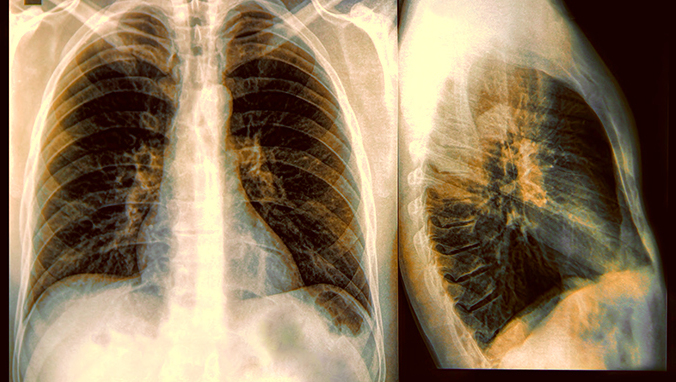

双肩痛是肺癌吗

很多人都有过肩膀痛的经历,有时候可能是因为炎症和肌肉损伤,但是还有一种可能性,频繁的肩膀痛可能是非鳞非小细胞肺癌的早期症状。肺癌可以带来肩部的相关疼痛,一开始一个部位疼,慢慢的“窜”到另一部位。那么,双肩痛是肺癌吗?

间皮瘤是肺癌的一种类型,它的引起原因是长期暴露于化学物品中,研究发现,14%的间皮瘤患者伴随有肩膀痛,而且肩膀痛通常是这些病人的最初症状。肺上沟瘤在肺癌中并不常见,这一发病位置较靠近肩膀,因此也会引起剧烈的肩膀痛。转移性肺癌指的是癌症已经扩散到身体的其他部位。当肺癌扩散到附近的地区,如骨头,淋巴结,和其他附近的结构,都可能发生肩膀痛。